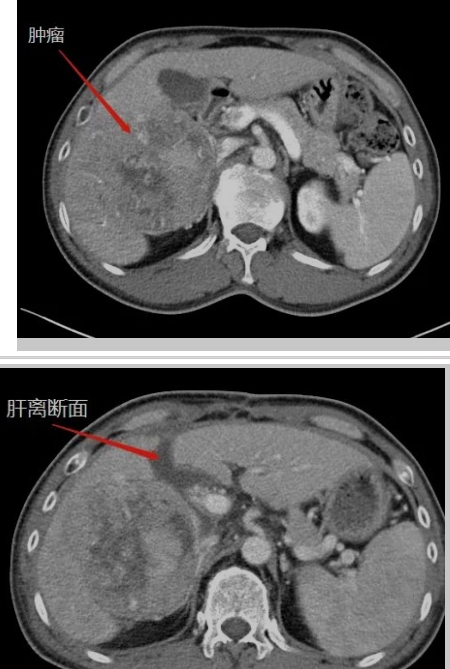

在生命的长河中,每个人都在与时间赛跑,与命运抗争。而对王晚期肝癌患者来说,这场赛跑尤为艰难,这场抗争格外惊心动魄。还记得四年半以前,当40多岁的王先生被确诊为晚期肝癌伴乙肝、肝硬化时,绝望的阴霾笼罩着整个家庭。对王先生来说,那是一段黑暗的日子,对未来的恐惧,对生命的不舍,尤其对年幼的孩子的不舍,让他...